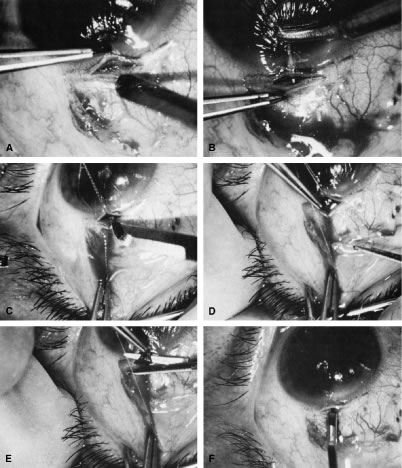

irrigated away, and chamber deepening cannot readily be performed.  Fig. 10. Peripheral iridectomy with the use of a preplaced suture to retract the

edges of the incision. A. An incision is made through two thirds of the thickness of the sclera

directly at the corneoscleral sulcus. B. A 9-0 white virgin silk suture is placed so that it will be able to be

retracted from the depths of the incision. C. The suture is looped and used to retract the edges of the incision superiorly

and inferiorly. The incision is completed, permitting prolapse

of a small knuckle of iris. D. The iris is grasped with a fine-toothed forceps. E. The iris is pulled over the blade of the DeWecker scissors; after the

position of the iris is noted, the blades are closed and the tissue is

excised. F. The tip of an irrigator is placed just inside the incision, with care

taken to ensure that it does not enter the anterior chamber. Remnants

of the pigment epithelium are flushed away, and the iris is permitted

to return to its proper position so that the pupil is completely round. (Spaeth GL. Glaucoma surgery. In Spaeth GL (ed). Ophthalmic Surgery: Principles

and Practice. Philadelphia: WB Saunders, 1990.) Fig. 10. Peripheral iridectomy with the use of a preplaced suture to retract the

edges of the incision. A. An incision is made through two thirds of the thickness of the sclera

directly at the corneoscleral sulcus. B. A 9-0 white virgin silk suture is placed so that it will be able to be

retracted from the depths of the incision. C. The suture is looped and used to retract the edges of the incision superiorly

and inferiorly. The incision is completed, permitting prolapse

of a small knuckle of iris. D. The iris is grasped with a fine-toothed forceps. E. The iris is pulled over the blade of the DeWecker scissors; after the

position of the iris is noted, the blades are closed and the tissue is

excised. F. The tip of an irrigator is placed just inside the incision, with care

taken to ensure that it does not enter the anterior chamber. Remnants

of the pigment epithelium are flushed away, and the iris is permitted

to return to its proper position so that the pupil is completely round. (Spaeth GL. Glaucoma surgery. In Spaeth GL (ed). Ophthalmic Surgery: Principles

and Practice. Philadelphia: WB Saunders, 1990.)